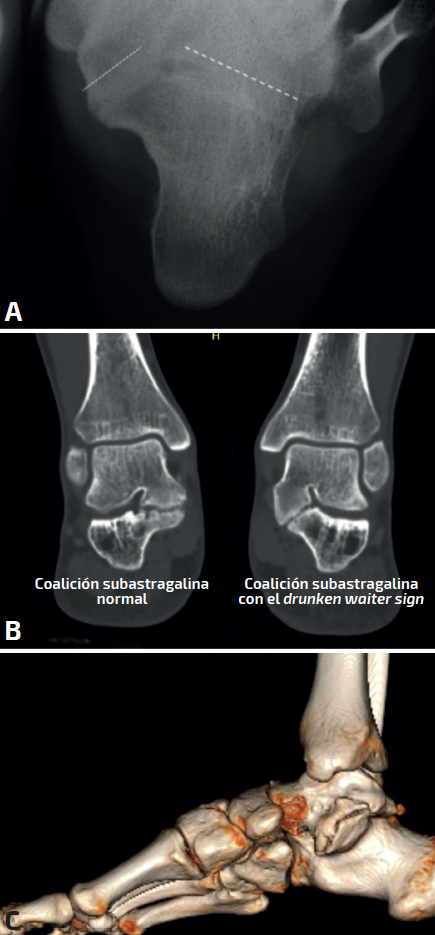

Figura 5. En la proyección axial se intuye la falta de paralelismo entre las superficies articulares. A: en la tomografía axial computarizada se aprecia coalición bilateral, con el drunken waiter sign, en uno de ellos (la bandeja del camarero se inclinaría); C: en la reconstrucción tridimensional se aprecia importante deformidad en el sustentaculum, donde el paciente refería dolor y deformidad.

Drunken waiter sign o signo del “camarero borracho” (Figura 5): si se aprecia en las radiografías axiales del calcáneo de Harris un ángulo superior a 20° entre la superficie del sustentaculum y la posterior, se sospechará una coalición, con una sensibilidad del 72% y una especificidad del 94% que se debe confirmar en cortes coronales de TAC.